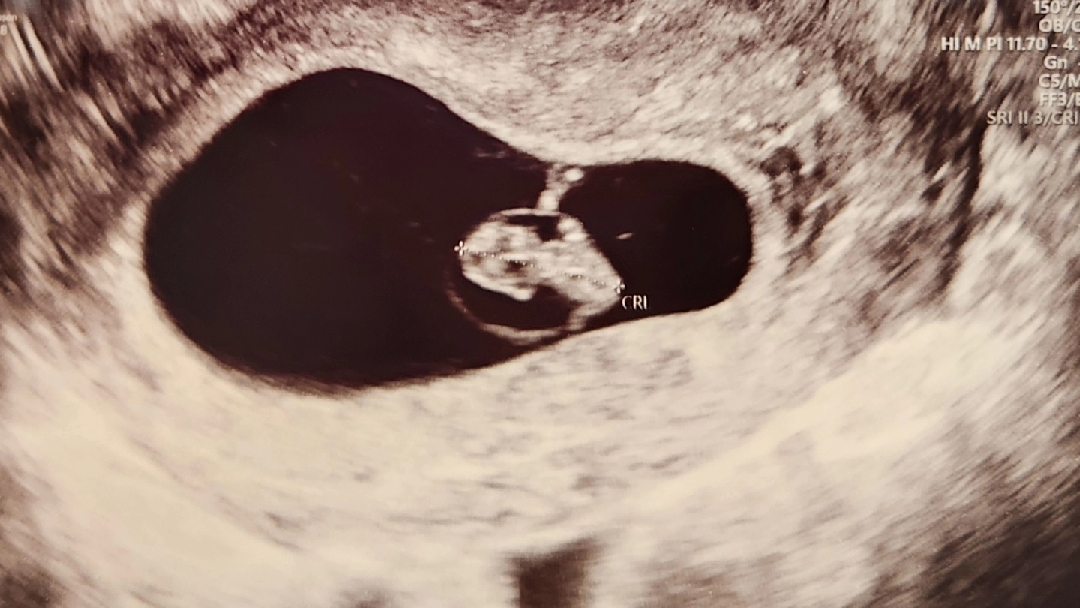

7주6일 드디어 심소듣고왔어요

남편 반차 쓰게해서 같이갔는데 진짜.. 손톱만한애기 심장이 이렇게 우렁차나요 ㅠㅠ 눈물찔끔났는데 꾹 참느라 죽는줄알았습니당 엄마가된다는건 정말 멋지고 신비로운일들의 연속이네요 ♡(입덧빼고..)